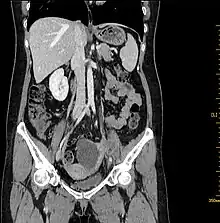

Abdominal CT. Cystic solid mass was detected on the left adnexal and the solid components were enhanced[5]

Computed tomography (CT) scans is a diagnostic x-ray procedure that generates detailed cross-sectional images of the body, facilitating the detection of potential ovarian cancer spread to other organs.[16] While CT scans may not effectively visualize small ovarian tumors, they have the capability to detect larger tumors and evaluate their potential invasion into nearby structures. Additionally, CT scans can identify enlarged lymph nodes, signs of cancer spreading to the liver or other organs, and indications of an ovarian tumor impacting the kidneys or bladder. Although CT scans are not commonly used for biopsying ovarian tumors, they can be utilized in the biopsy of suspected metastases through a technique known as CT-guided needle biopsy.[16]

The difficulty in screening for SCC revolves around the creation of effective strategies with a positive predictive value. The timing aspect is crucial due to the lack of a specific timeframe for the onset of invasive disease or the interval stage between stage I and stage III carcinomas.[17] Ultrasound screening provides a detailed view of the ovaries, identifying morphologic changes as potential signs of malignancy. Key diagnostic factors include the presence of abnormalities, ovarian size, blood flow, and abdominal/pelvic fluid. The persistence of abnormalities after four to six weeks may decrease the occurrence of false positives. Screening protocols, often based on morphologic indices, utilize transvaginal ultrasound findings like cyst wall structure, septation, papillary projections, echogenicity, and ovarian volume to effectively detect malignancy.[17]